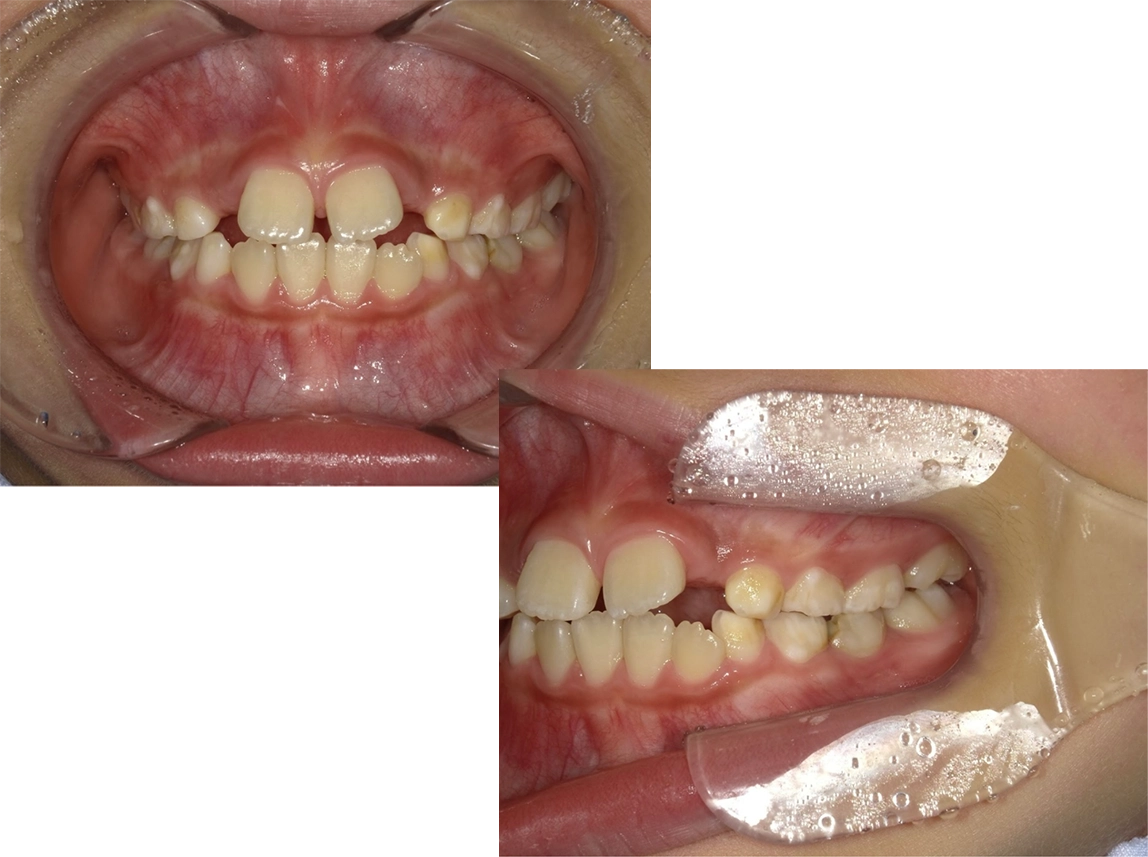

治療前

治療後

| 術名 | 小児矯正の症例 |

|---|---|

| 年齢 | 12歳 |

| 性別 | 女児 |

| 主訴 | 前歯の凹凸 |

| 診断名 | 下顎前突・叢生 |

| 治療内容 | 顎顔面矯正 |

| 治療期間 | 26ヶ月 |

| 費用 | 50万+税 ※別途月々の調整料(5500円)がかかります |

| リスク・副作用 | 疼痛・咬合違和感、等 |